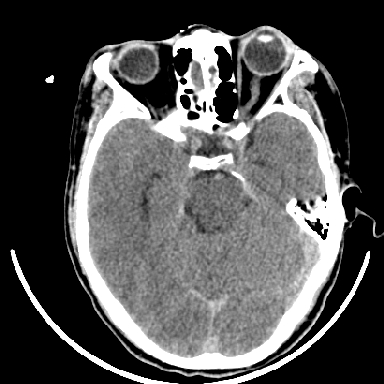

标题: CT6056:脑出血(血管畸形?) [打印本页]

标题: CT6056:脑出血(血管畸形?)

m 40突发头痛左侧偏瘫3小时

另附部分资料:“血液溢出血管外形成血肿,其内含有大量血红蛋白、血浆白蛋白,球蛋白,因这些蛋白对x线的吸收系数高于脑质,故ct呈现高密度阴影,ct值达40~90h,最初高密度灶呈非均匀一致性,中心密度更高,新鲜出血灶边缘不清。基底节区血肿多为“肾”型,内侧凹陷,外侧膨隆,因外侧裂阻力较小,故向外凸,其它部位血肿多呈尖圆形或不规则形”

术中抽出40ml陈旧血液,血肿底部似见一条索血管影